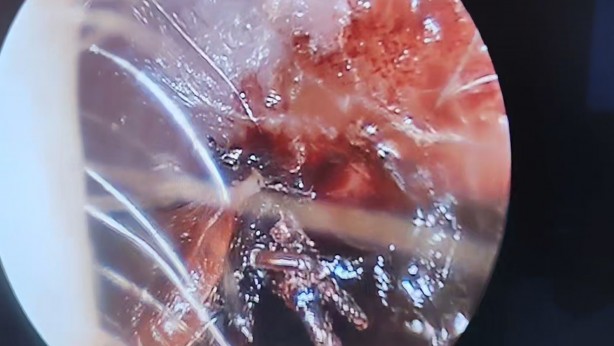

70 yaşındaki kadının kulağında hareket eden kene görüldü

Bitlis’in Tatvan ilçesinde 70 yaşındaki kadın hastanın kulağına giren kene başarıyla çıkartıldı. Tatvan ilçesinin bir köyünde yaşayan 70 yaşındaki kadın hasta, sabah uyandığında kulağında bir şeylerin hareket ettiğini hissetti. Tatvan Devlet Hastanesi acil servisine başvuran kadın hasta, doktorların kulağında hareket halinde olan keneyi tespit etmesinin ardından Kulak Burun Boğaz Hastalıkları Uzmanı Operatör Dr. Hakan Tuhan’a sevk etti. Op. Dr. Hakan Tuhan, kısa süreli operasyonla 70 yaşındaki kadın hastanın kulağında hareket halinde olan keneyi başarıyla çıkarttı. 10 gün boyunca takibi yapılan hasta sağlığına kavuşarak taburcu oldu.